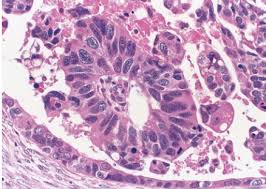

Diagnosis And Management Of Ovarian Cancer American Family Physician

Diagnosis And Management Of Ovarian Cancer American Family Physician from www.aafp.org